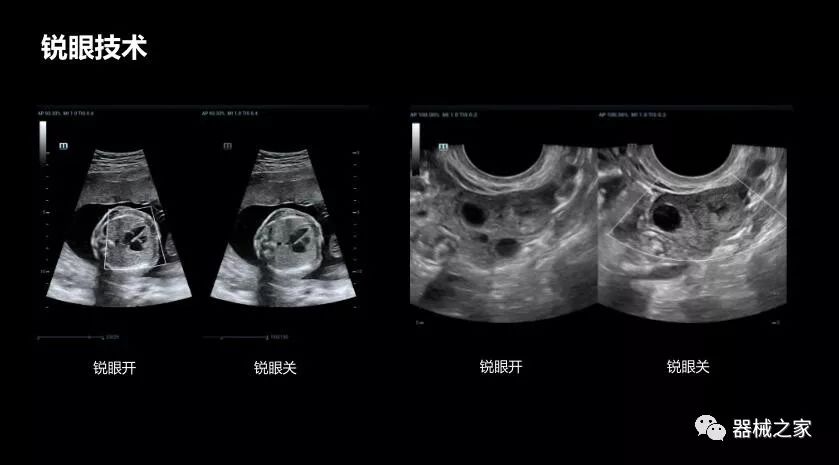

銳眼技術

做胎兒心臟檢查的時候,如果是聲窗不好的孕婦,很難看清胎兒心腔 。女媧Resona 8的銳眼技術能很好的優(yōu)化心腔內的噪聲,讓胎心結構完美的呈現(xiàn)。